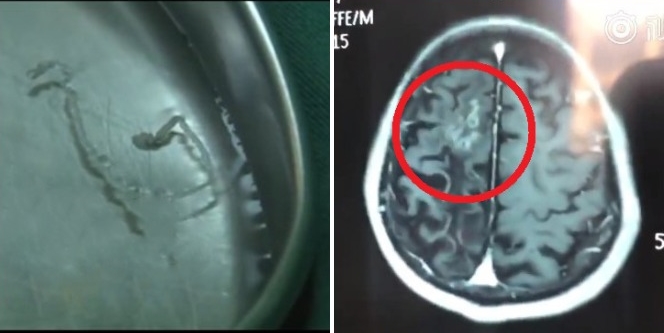

Giun dài 10 cm sống ký sinh trong não người đàn ông suốt 30 năm.

Sau khi chụp X-quang, bác sĩ cuối cùng tìm ra thủ phạm gây ra đau đầu kéo dài cho người đàn ông suốt 30 năm qua là một con giun dài 10 cm sống ký sinh trong não. Sự xuất hiện của nó khiến bệnh nhân bị đau nửa đầu mãi không dứt.

Các bác sĩ đã loại bỏ con giun ra khỏi hộp sọ ông Zhang một cách an toàn. Kinh ngạc, sinh vật này vẫn còn ngoe nguẩy trong khay y tế khi được lấy ra ngoài.